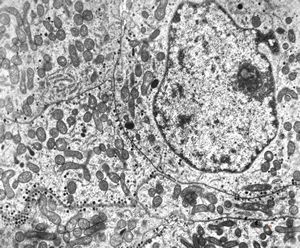

F,50y. | progressive multifocal leukoencephalopathy- viral particles in a glial cell